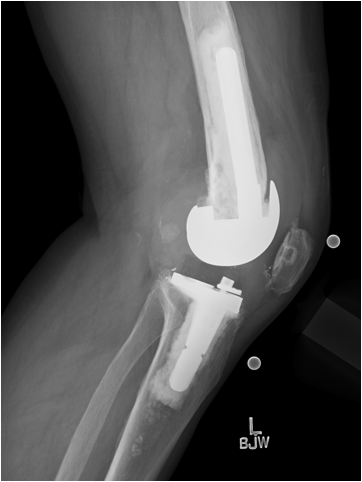

Case: 61 yo F w/ painful right revision TKA after a fall. Elevated serum Co, Cr. Not infected. Treatment of the femur? Management of well-fixed TM tibial cone?

Signficant metallosis in the joint and osteolysis about the femoral condyles. Cement-in-cement revision to DFR with retention of well-fixed TM tibial cone. Data on outcomes of retained, well-fixed cones coming in 2023!